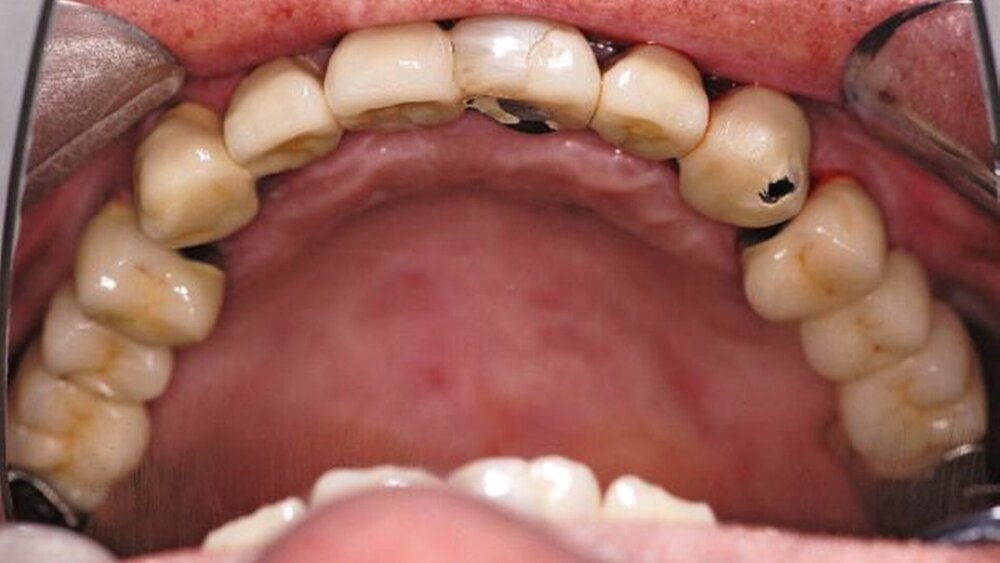

Im Rahmen der intraoralen Befunderhebung wurde festgestellt, dass die Gingiva insgesamt gerötet und ödematös war. Die Messung der Taschentiefe ergab einen durchschnittlichen Wert von fünf mm. Der ermittelte PSI (in Bezug auf die Sechstanten) ergab die Werte 4, 2, 4, 3, 2, 2. Pusaustritt konnte in regio 17 und in regio 27 festgestellt werden, so dass der Erhalt dieser Zähne fraglich war. Im Oberkiefer lag ein prothetisch versorgtes Lückengebiss der Kennedy-Klasse III2 vor. Die Zähne 18, 16, 15, 11, 25, 26 und 28 fehlten. Die prothetische Versorgung bestand aus einer Brücke 17 bis 14 zum Ersatz von 16 und 15, einer Brücke 13 bis 23 zum Ersatz von 11 und einer Brücke 24 bis 27 zum Ersatz von 25 und 26. Sämtliche Brückenanker wiesen Randundichtigkeiten und Sekundärkariesbildung auf. An 21 konnte eine großflächige Keramikabplatzung festgestellt werden. 17 und 27 reagierten im Perkussionstest stark positiv. Im Rahmen einer Sensibilitätsprüfung mittels CO2-Schnee reagierten die Zähne 17, 22 und 27 negativ. Im Unterkiefer lag ein Gebiss der Kennedy-Klasse II3 vor. Die Zähne 38, 36, 34, 44, 45, 47 und 48 fehlten. Die Zähne 37, 42, 46 waren mit Füllungen versorgt, die erhebliche Undichtigkeiten aufwiesen. 46 reagierte im Kältetest negativ. Alle Unterkieferzähne wiesen starke Attritionen auf. Diese Zähne 33 bis 43 sowie 37 und 35 reagierten im Kältetest stark schmerzhaft (Abbildungen 4, 5).